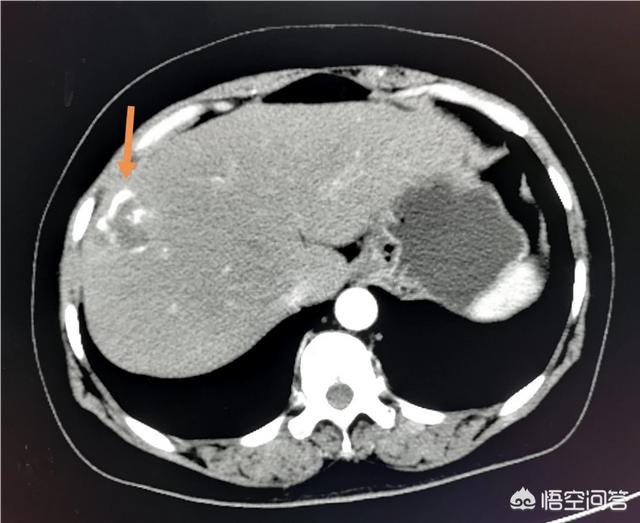

例えば、私は画像診断医で、肝嚢胞や腎嚢胞のフィルムを毎日見ています。これらのフィルムを長期にわたって観察し、年に1回検査を受けに来ると、多くの人の嚢胞は基本的に変化せず、中には縮小したり肥大したりするものもあるが、悪性化するものはほとんどない。長期間の観察により、実際には無症状の嚢胞が安定し、変化しないこともあることがわかりました。

しかし、診察の結果、肝臓に病変が見つかり、その病変は非常に小さいものである必要があるが、経験上、これはゆっくりと成長し、最終的には転移する可能性のある悪性のものである可能性がある。その場合、医師は治療を勧めるだろう。後で体に取り返しのつかないダメージを与えることを考慮するからである。

また、腫瘍が大きく、圧迫症状が出ている場合は、良性であっても外科的に切除する必要があります。例えば、肝嚢胞が5cmを超え、周囲の肝組織を圧迫し、痛みを伴う症状を示している場合も外科的に治療する必要があります。

例えば、この2.5cmの肝血管腫は非常によく見られるもので、1~2年ごとに超音波検査を受けるのがよいでしょう。